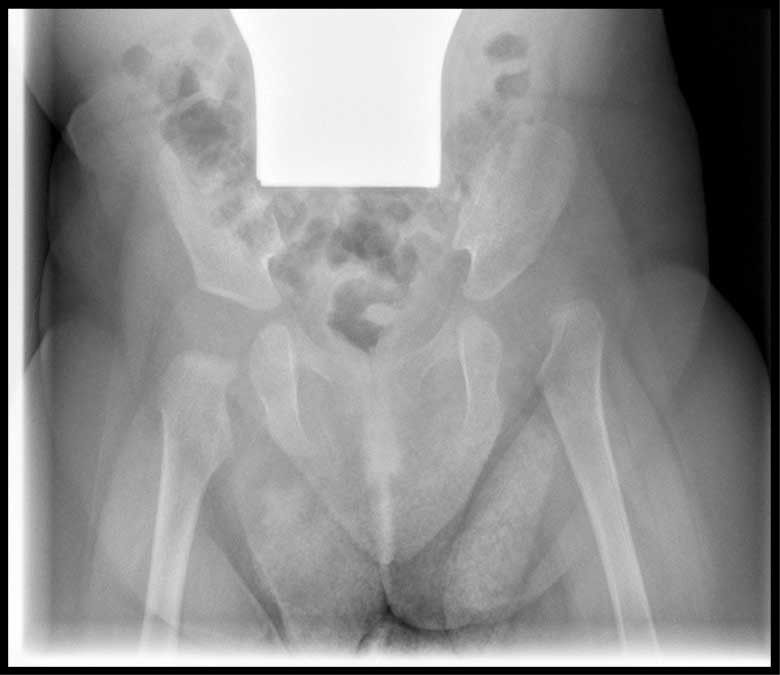

Auffällig ist die

schlechtere Überdachung des Hüftkopfes im Vergleich zur Gegenseite und eine schräger verlaufende

Stellung des Pfannendaches, die zu einer vermehrten mechanischen Belastung des Knorpels der Hüfte

führt.

Auffällig ist die schlechtere Überdachung des Hüftkopfes im Vergleich zur Gegenseite und eine schräger verlaufende Stellung des Pfannendaches, die zu einer vermehrten mechanischen Belastung des Knorpels der Hüfte führt.